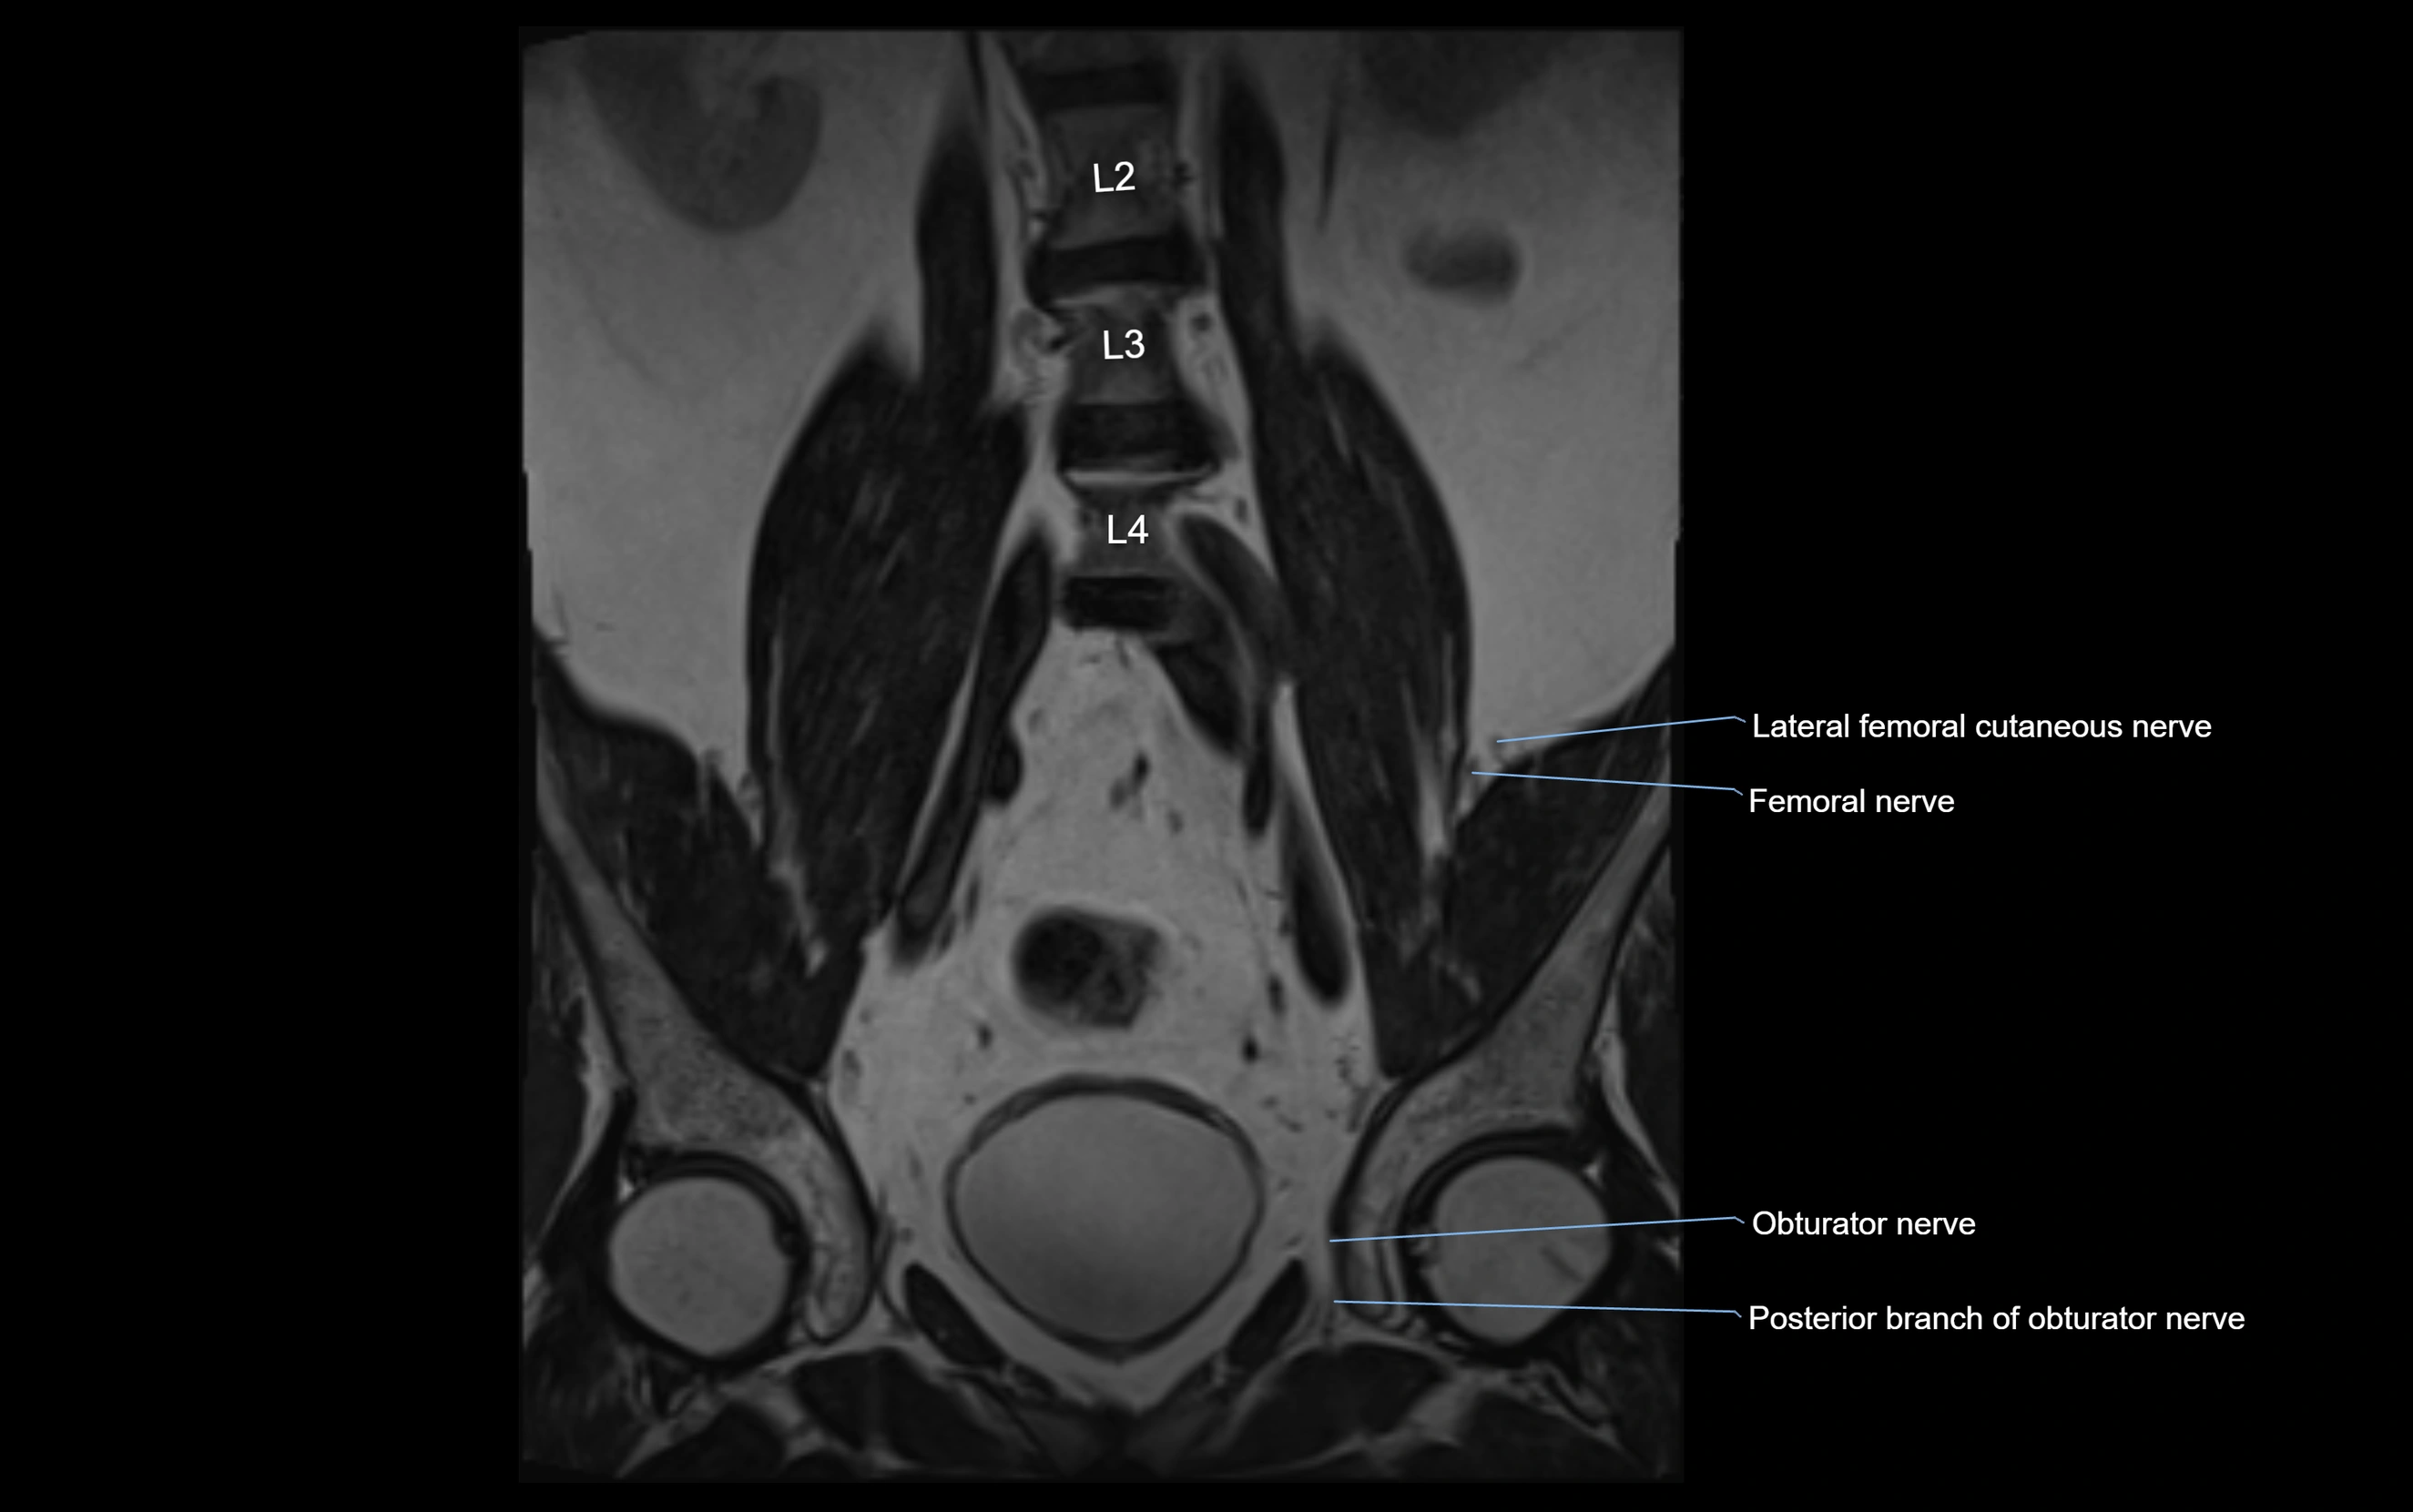

MRI image

image